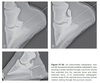

Abaxial nonarticular fractures are usually difficult to recognize because they are normally only minimally displaced.

Figure 91-42. (A) Palmaro-45-degree proximal-45-degree lateral-dorsodistal oblique radiographic view of a lateral Type I fracture of the pedal bone 2 days after fracture occurrence. (B) Palmaro-45-degree proximal-45-degree lateral-dorsodistal oblique radiographic view of a lateral Type I fracture of the pedal bone 2 months after fracture occurrence.

Figure 91-44. (A) Radiograph of a Type II pedal bone fracture 4 days after fracture occurrence. (B) Radiograph of a Type II pedal bone fracture 12 months after fracture occurrence; there is delayed union and malunion. Frequently, a delayed union, malunion or nonunion with chronic lameness can be observed after conservative therapy (Figure 91-44).